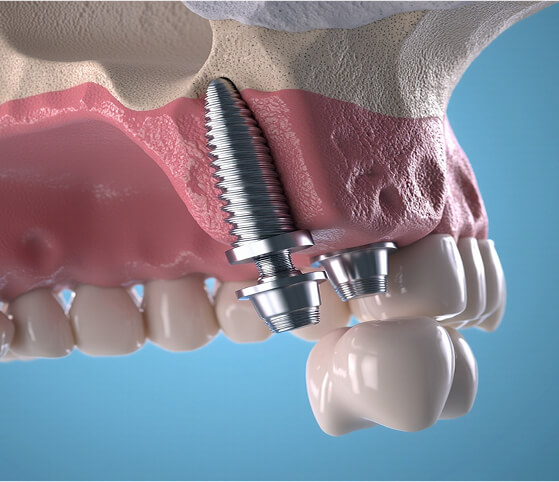

Ahogy a saját fogát, úgy az implantátumot is a csont tartja a megfelelő, stabil pozícióban. Emiatt fontos, hogy az implantáció a lehető leggyorsabban megtörténjen a fog elvesztése – és a seb gyógyulása – után. Ahogy az is fontos, hogy az implantátum erős alapra épüljön.

A csontpótlás biztosítja a megfelelő csontszélességet és vastagságot, hogy az implantátumok behelyezhetők legyenek, stabilan rögzüljenek.